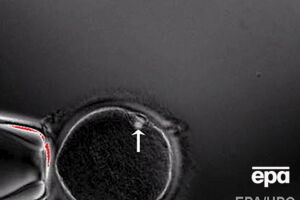

Ученым удалось вырастить гибридный эмбрион человека и свиньи